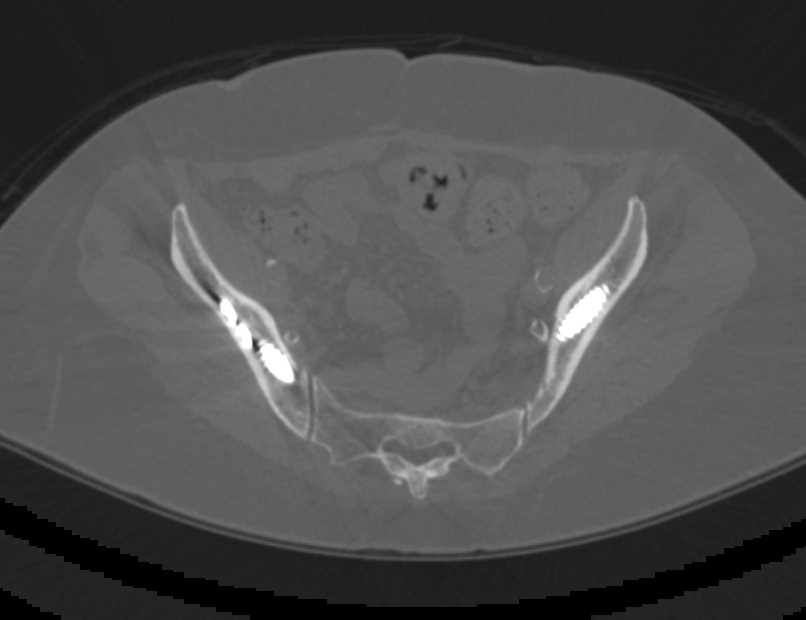

Diagnosis

Hemangioma Right Thigh